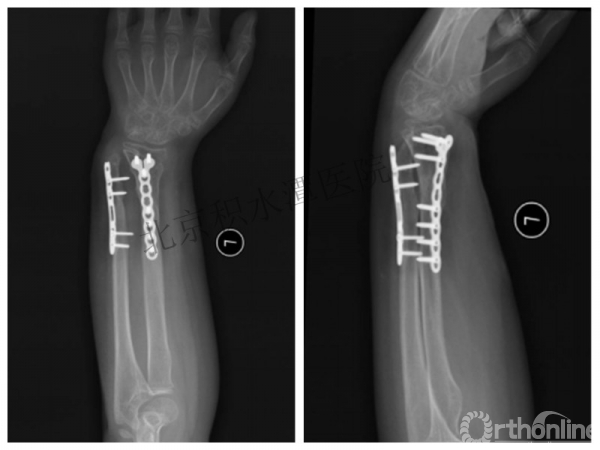

医生的处理方法!——医生终于没有坚持自己的原则!

伤后40天—切开复位内固定!

伤后18个月

如何面对?

手术历时近 5小时!心情之压抑无以言表!因为当时的经治医生是他们的进修生!感觉是他们的失职甚至渎职!

唯一可以肯定—预后不佳!郭教授是党员!是无神论者!但是很诡异的事情:手术中发生—C形臂看不清!拍片条件总是调节不好!手术器械换了三套!内固定钢板总不合适!

术后15月,虽然家长满意了,但是他们医生不满意!